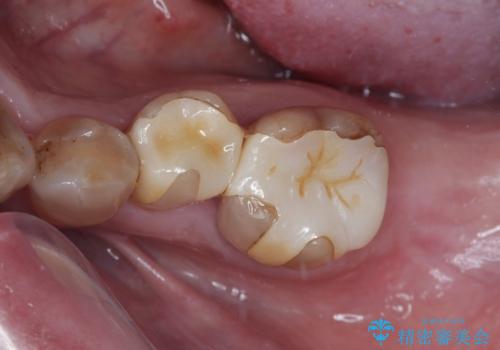

- 左下奥歯のインプラント治療と左上の被せもののやり替えを希望されて来院された患者様です。

左上の奥2本は他院で根管治療と仮歯まで入れている状態です。根管治療のやり替えは希望されなかったため被せものから治療していくことにしました。

その手前の小臼歯は根尖病変が認められるため根管治療のやり直しからしていくこととしました。

左下はインプラントによる補綴治療を行いました。